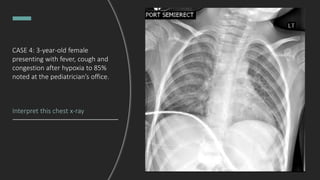

CASE 4: 3-year-old female

presenting with fever, cough and

congestion after hypoxia to 85%

noted at the pediatrician’s office.

Interpret this chest x-ray

CASE 4: 3-year-old female presenting

with fever, cough and congestion

after hypoxia to 85% was noted at

the pediatrician’s office.

Bilateral perihilar interstitial and

peribronchial thickening, representing

edema versus a worsening viral

process versus reactive airway

disease.